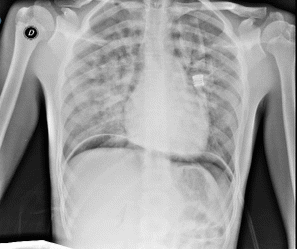

Dopo 24 ore di ossigenoterapia, il paziente mostrava un rapido miglioramento clinico e radiologico (Figura 2), tanto da essere dimesso dopo sei giorni.

Figura 2. Rx torace a 48 h: appaiono rischiarati entrambi I campi polmonari dove non si apprezzano significativi ad-densamenti parenchimali né versamenti pleurici.